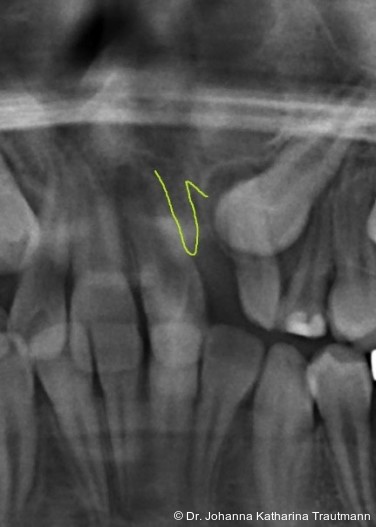

Das Fernröntgenseitenbild zeigte eine skelettale Klasse IIAnomalie mit einem Wits von 5,6 mm, bei einer tiefen Konfiguration (ML NL = 16,5°) mit bialveolär retrudierten Fronten (OK1NA = 5,9°; UK1NB = 10,4°), was sich auch in der Modellanalyse widerspiegelte. Hier zeigte sich zudem ein schmaler Oberkiefer mit multiplen Kippungen und Rotationen in der Front, einem hypoplastischem 22 sowie einer Mesialwanderung des 16. Des Weiteren zeigte sich eine asymmetrische Bisslage mit 1 PB distal rechts und ½ PB distal links bei einem Overjet von 2,5 mm sowie einem Overbite von 5 mm. Während im Unterkiefer bereits die zweite Zahnwechsel phase begonnen hatte, zeigte sich im Oberkiefer noch kein Wechsel in den Stützzonen. Gerade bei Patienten mit Spaltbildungen ist eine engmaschige Überwachung des Durchbruchs der oberen Eckzähne essenziell. Während bei der Allgemeinbevölkerung die Prävalenz von verlagerten Eckzähnen bei ca. 2,8 Prozent liegt2, ist diese bei Patienten mit Lippen-Kiefer-Gaumen-Spalten um den Faktor 10 erhöht.3, 4 Als klassische Risikofaktoren gelten zudem Platzmangel, transversale Enge aber auch Fehlstellungen, Nichtanlagen oder Hypoplasien der zweiten Schneidezähne. Diese übernehmen normalerweise die Funktion der Leitschiene für den S-förmigen Durchbruch der Eckzähne. Im vorliegenden Patientenfall kommen also mehrere Risikofaktoren für eine Verlagerung zusammen, was die rechtzeitige Diagnostik zur Abklärung einer Durchbruchsproblematik rechtfertigt. Da im Spaltbereich auch zusätzlich ein ausgeprägtes Knochendefizit vorliegen könnte, sollte auch immer die Option einer sekundären Osteoplastik abgewogen werden, deren Indikation und Timing optimal zum Durchbruch der Canini angepasst werden sollte.5

Zur genaueren Diagnostik der Lage beziehungen der Eckzähne und des Knochenangebotes im Spaltbereich kann neben den kieferorthopädi schen diagnostischen Unterlagen laut der S2 kLeitlinie Dentale digitale Volumentomografie6 auf eine dreidimensionale Bild gebung zurückgegriffen werden. In dieser zeigte sich eine vestibuläre Verlagerung des 13, eine palatinale Verlagerung des 23, sowie ein deutliches Knochendefizit im Spaltbereich mesial des hypoplastischen 22 (Abb. 2). Nach Auswertung der 3D-Daten erschien aufgrund der palatinalen Lage des 23 eine invasive Operation wie eine sekundäre Osteoplastik keinen entscheidenden Vorteil für die weitere Be handlung zu haben. In Rücksprache mit der Mund-Kiefer-Gesichtschirurgie der UMG wurde daher auf die OP verzichtet und initial die kieferorthopädische Therapie in den Vordergrund gestellt.